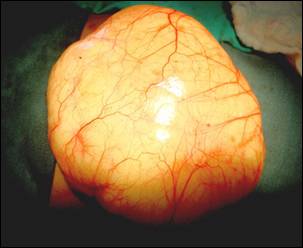

Image 3: Operative view of chylous cyst